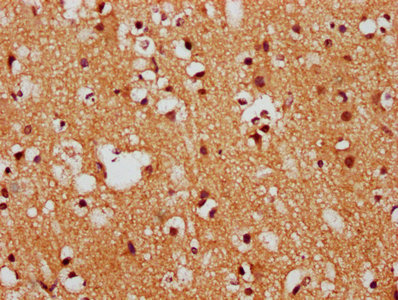

• IHC image of CSB-PA008602LA01HU diluted at 1:400 and staining in paraffin-embedded human brain tissue performed on a Leica BondTM system. After dewaxing and hydration, antigen retrieval was mediated by high pressure in a citrate buffer (pH 6.0). Section was blocked with 10% normal goat serum 30min at RT. Then primary antibody (1% BSA) was incubated at 4°C overnight. The primary is detected by a biotinylated secondary antibody and visualized using an HRP conjugated SP system.